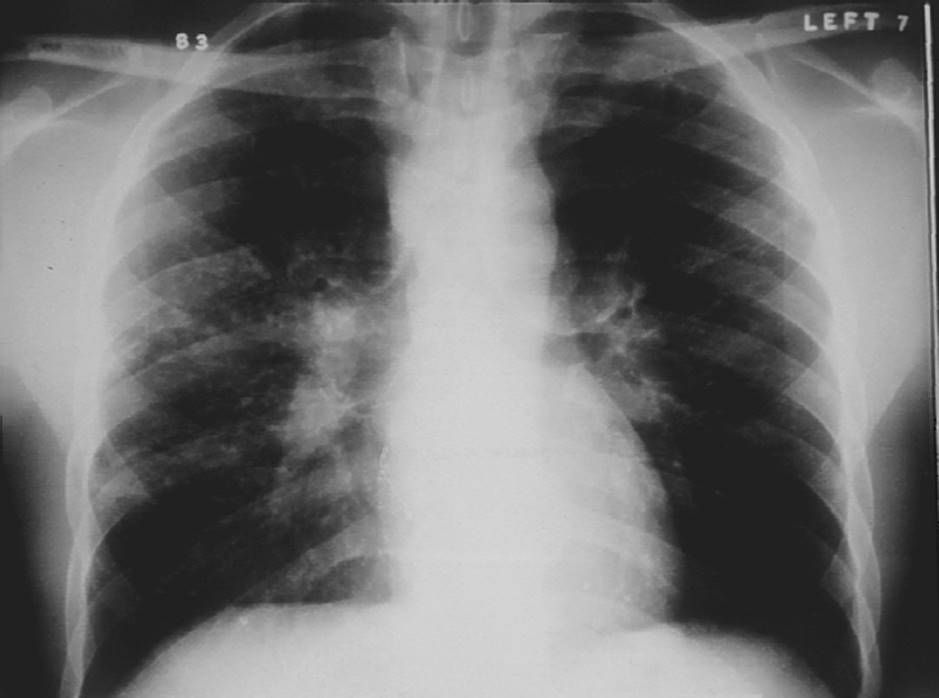

CF is the most common autosomal recessively inherited disorder in Caucasians.69 Within the lungs, this genetic defect leads to excessive production of thick, dehydrated, hyperviscous mucus and impairment of the mucociliary blanket.70,71 The incidence is 1 in 3,000 births in the United States and Europe. Chronic bouts of inflammation and infection lead to the breakdown of protein in the lungs. Obstructions of small airways develop from mucus plugs and destruction of the cartilaginous support of the airways. The end result is bronchiectasis, which is a permanent dilatation of the bronchi that is characterized by inflamed airways, which are full of purulent sputum23 (see Figs. 7-11and 7-12).

FIGURE 7-11 Cystic fibrosis. Notice the hyperinflation of the lung, the fibrotic changes throughout the lung fields, particularly the upper lobes, and decreased aeration. (Courtesy of Joseph Pilewshi, MD, University of Pittsburgh, PA.)